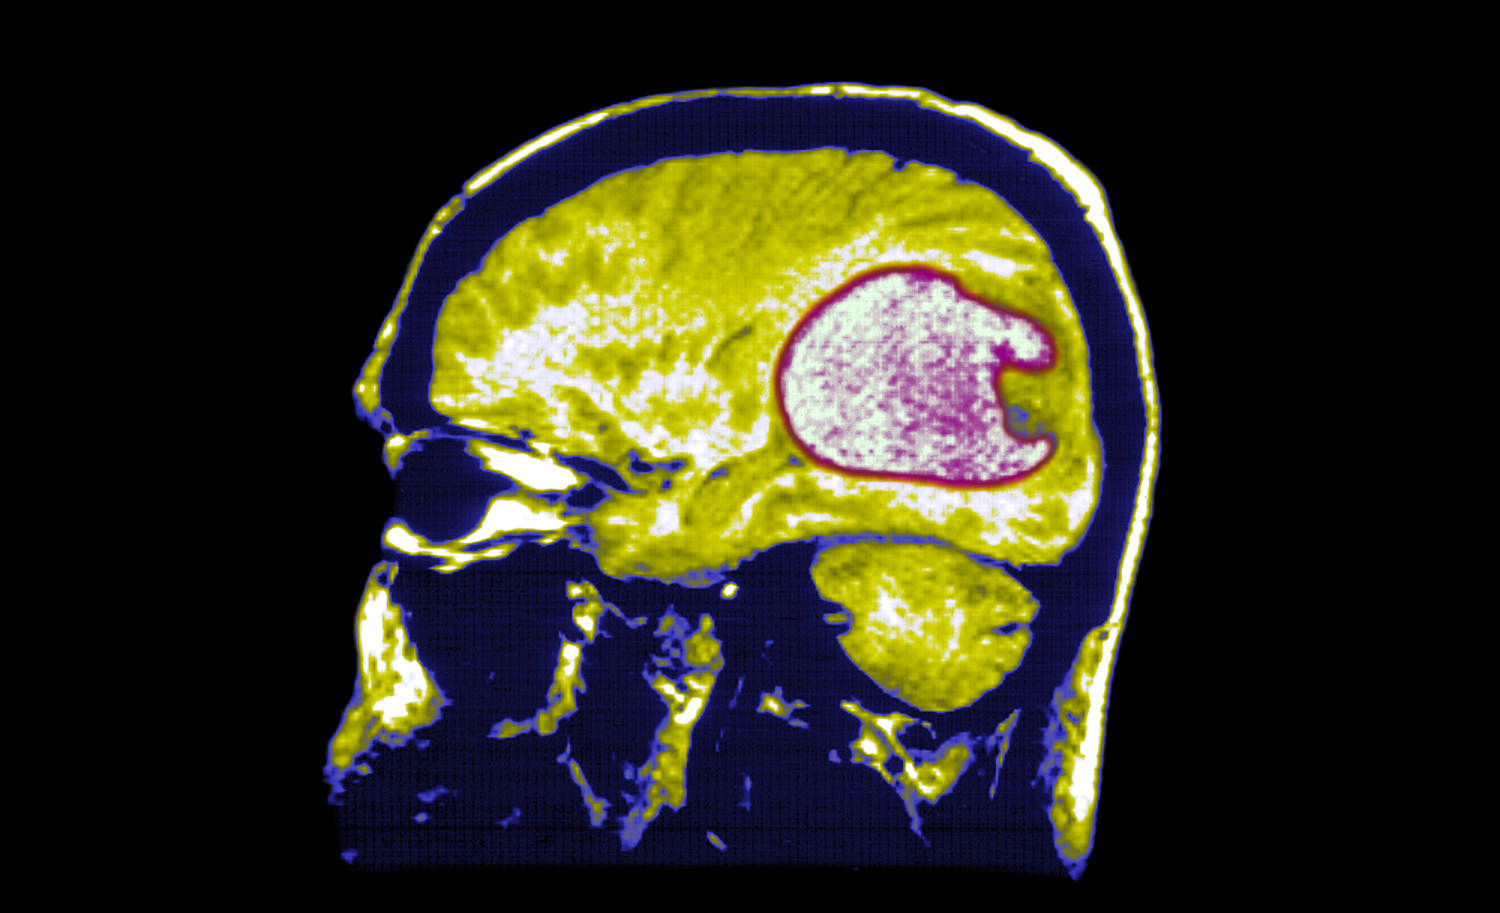

All three patients — two who were in their 70s and one in her late 50s — responded quickly to the treatment. Brain scans showed their tumors shrunk significantly within a day of receiving the therapy. In the 57-year-old woman, an MRI taken five days after her infusion of the modified cells showed her tumor was nearly gone.